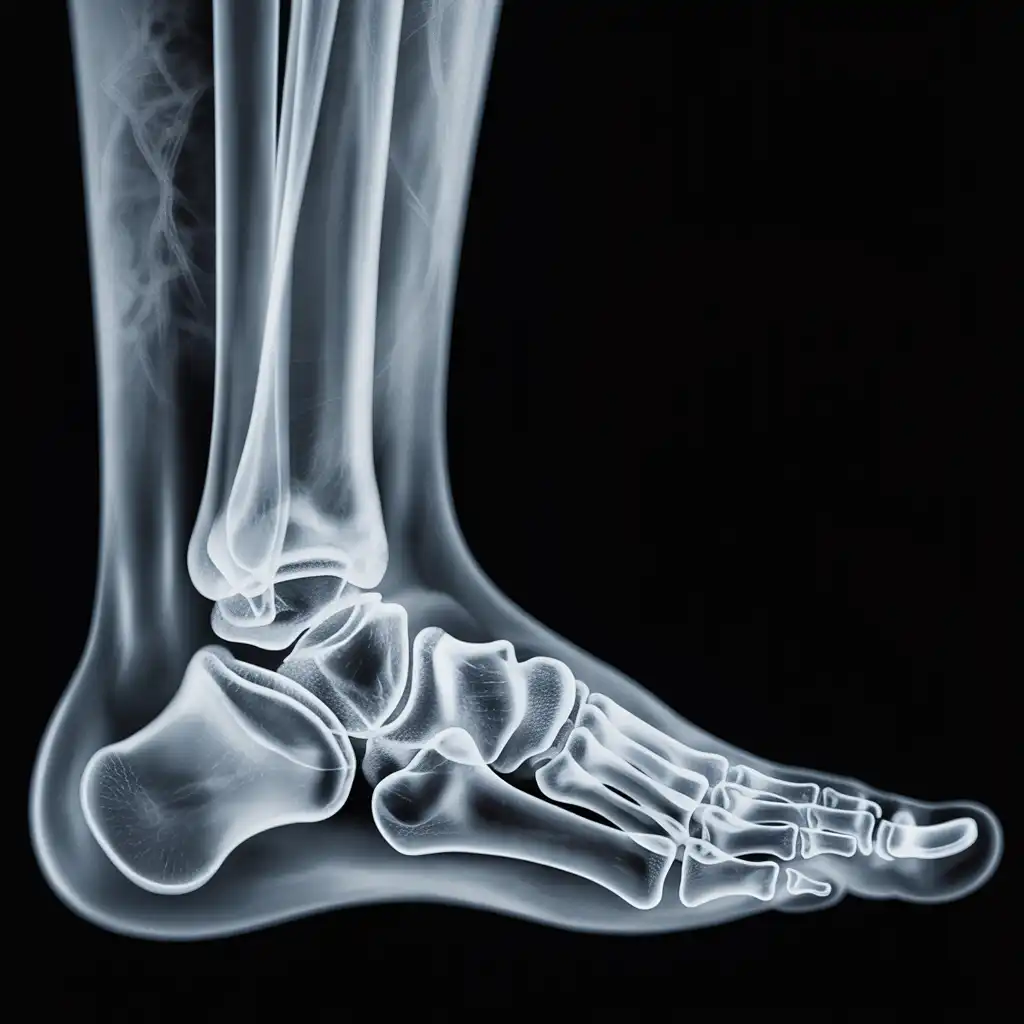

Da anni offriamo un servizio di radiografie a domicilio pensato per garantire ai nostri pazienti la stessa qualità diagnostica degli esami eseguiti in ospedale, ma con la comodità e la sicurezza della propria casa.

Abbiamo effettuato migliaia di esami direttamente presso abitazioni, residenze e strutture assistenziali, utilizzando apparecchiature digitali portatili certificate e procedure rapide e sicure.